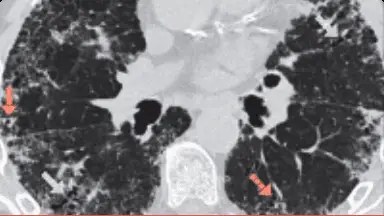

Curba Kaplan-Meier care demonstrează mortalitatea la pacienții cu FPI față de pacienții cu PID-AR subdivizată conform ghidurilor de diagnosticare ale FPI emise de Societatea Fleischner privind modelul HRCT.

Adaptat după: Jacob J et al. Eur Respir J. 2019;53:pii1800869

Modelul cert UIP în PID-AR (fagure de miere): 48% supraviețuire la 3 ani și 45% la 6 ani, n=55. Supraviețuirea medie 3,5 ani

Model probabil UIP în PID-AR (fără fagure de miere): 76% supraviețuire la 3 ani și 58% la 6 ani, n=56. Supraviețuirea medie 4,6 ani

Aspect PID-AR non-UIP: 92% supraviețuire la 3 ani și 75% la 6 ani, n=46. Supraviețuirea medie 5,3 ani

FPI: 42% supraviețuire la 3 ani și 18% la 6 ani, n=284. Supraviețuirea medie 2,9 ani